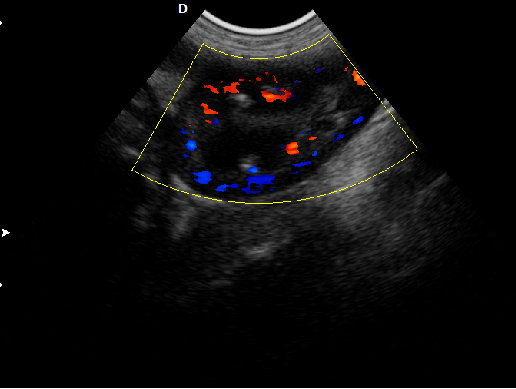

P5-VET獸用彩超機應用范圍:

·

適用于各種動物的臨床腹部、胸腔,心臟、肌腱、小器官、眼球、生殖系統等的檢查